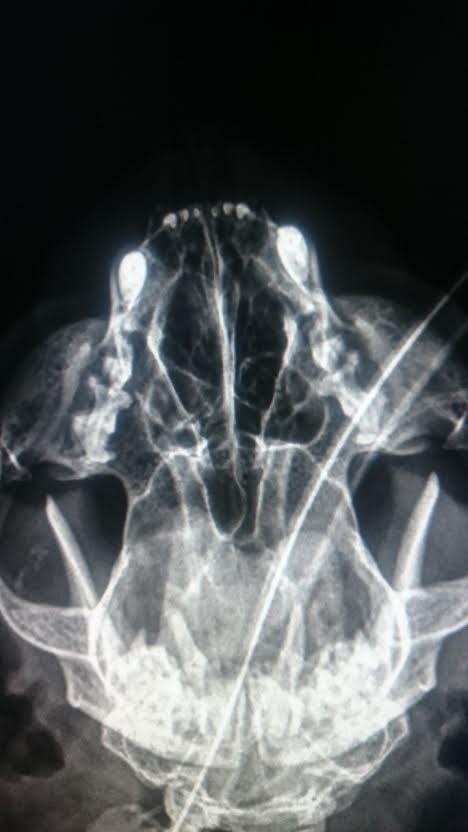

【灌洗狀況】

常見右側鼻膿

使用多種抗生素.消炎.化痰藥 無明顯效果

鼻腔灌洗 採樣鼻膿 細菌培養

灌洗時 無法直接由軟顎上方通至右側鼻道(左側則非常順暢)

懷疑右側鼻道後方可能有狹窄

細菌培養結果顯示目前使用的抗生素皆為有效的藥物

鑒於 抗生素等藥物無明顯效果

及懷疑鼻道結構異常

目前建議使用物理性移除鼻膿

當量大時 則進行鼻腔灌洗

今日沖出非常多鼻濃,但不知鼻腔的通暢能夠維持多久